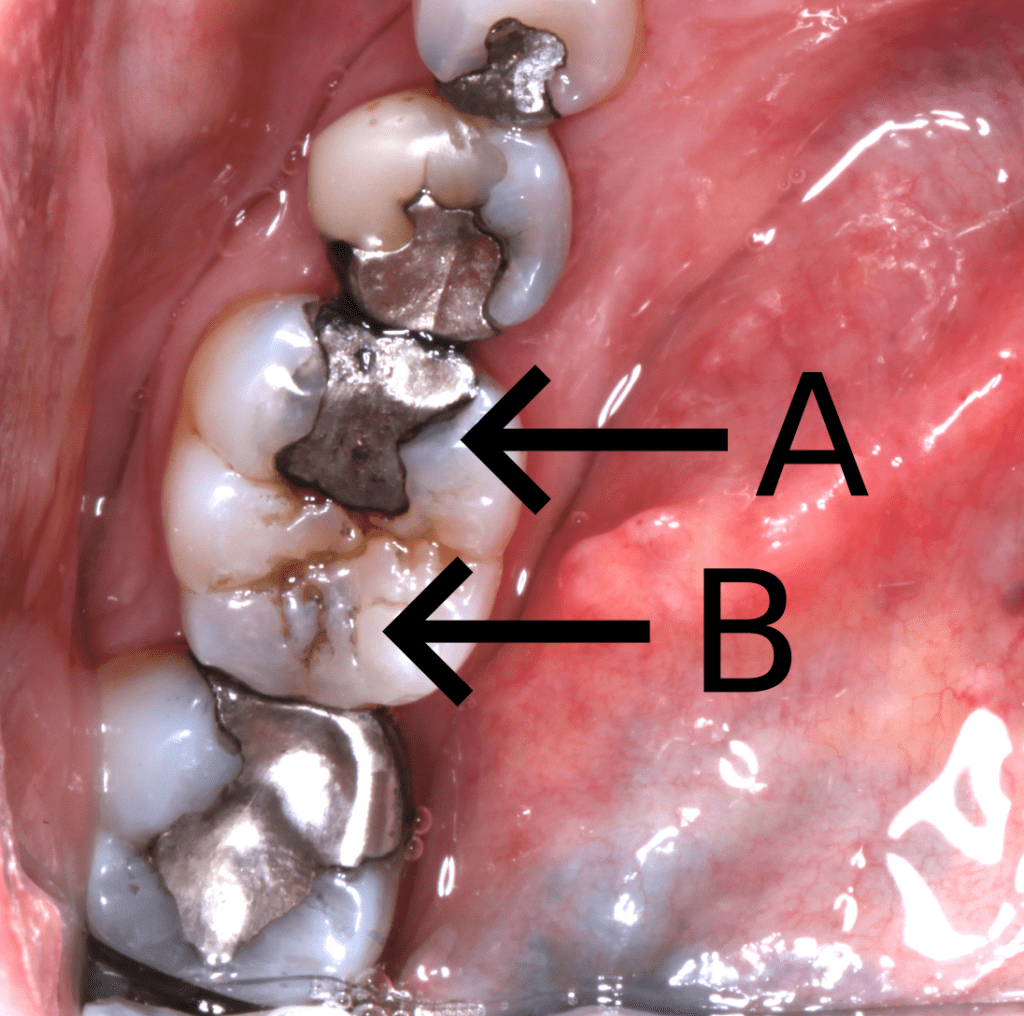

Note the shadowing around the fissure system of the second premolar and first molar, compared to the first premolar.

A. Shadowing caused by corrosion byproducts

B. Shadowing caused by caries

A. Sclerotic dentine, arrested caries

B. Secondary caries

C. Marginal leakage